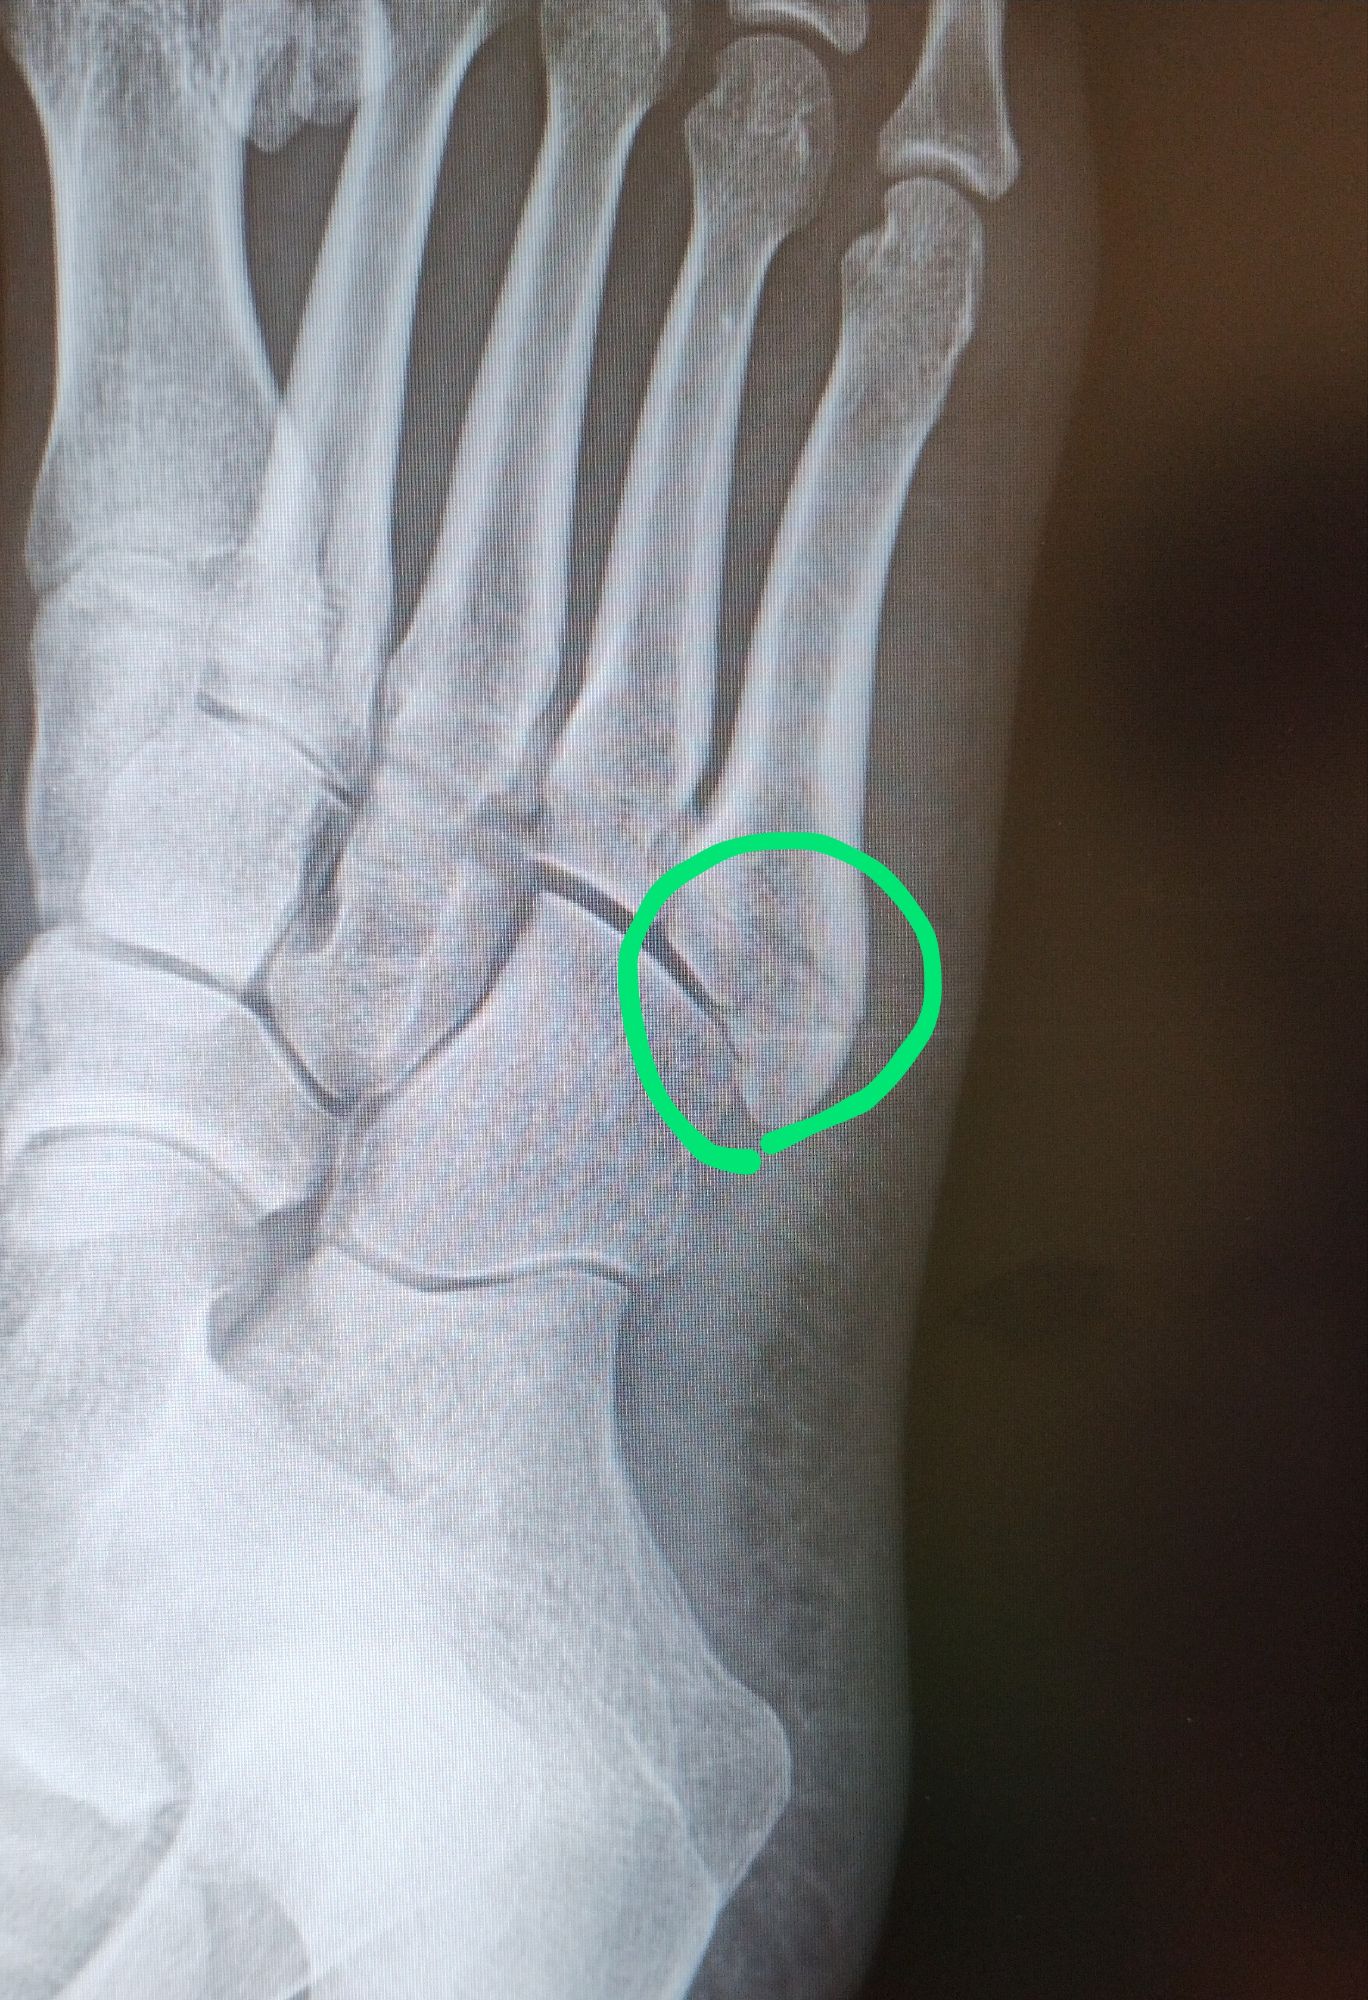

骨折中に作成が進む